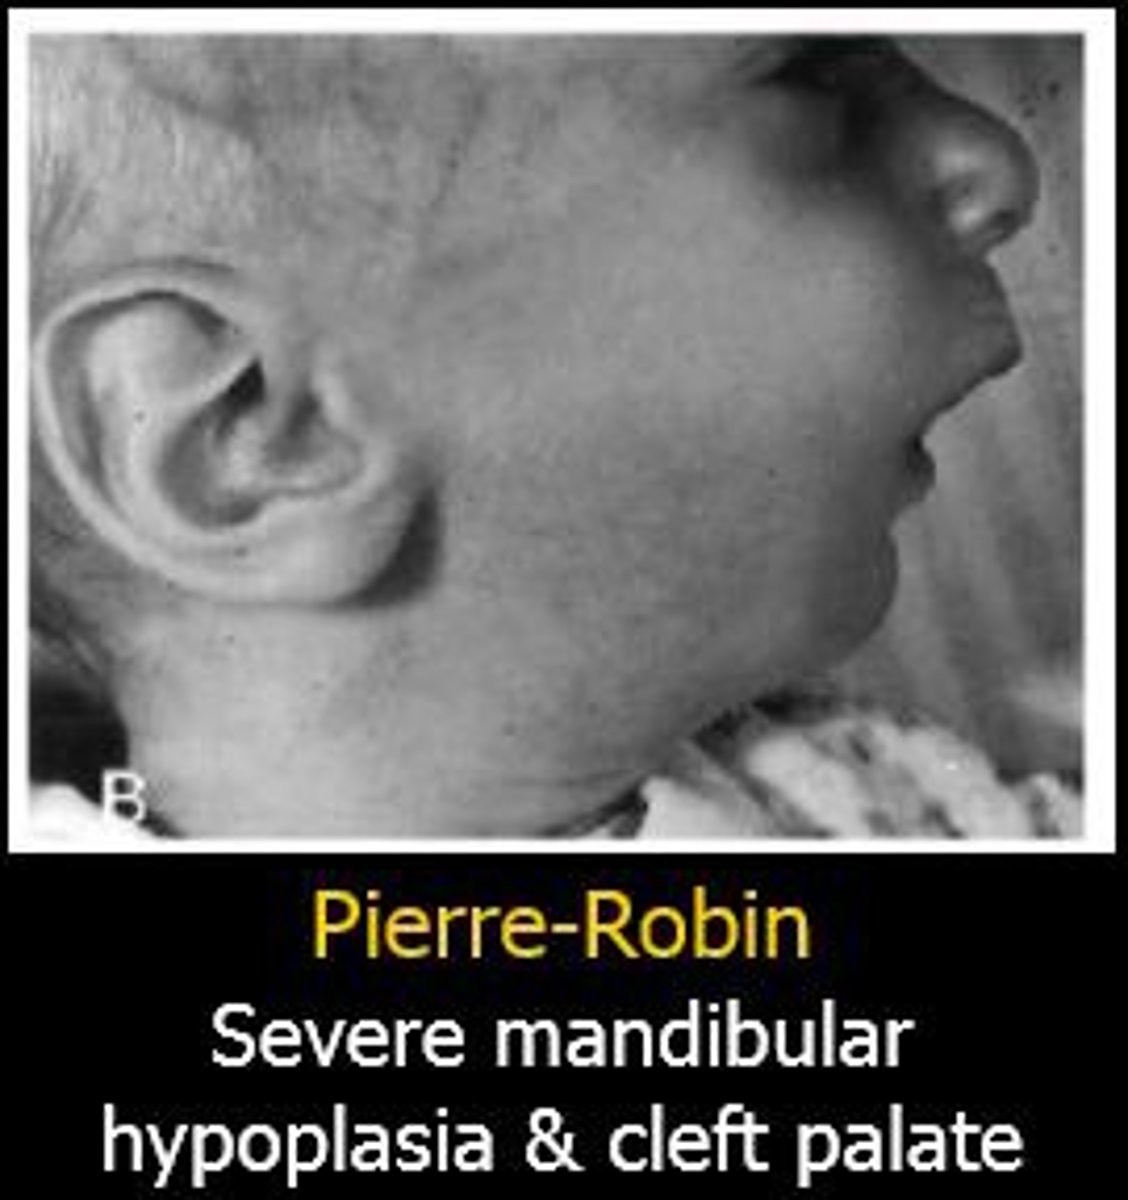

patient with cleft palate, mandibular micrognathia, glosspotopis (airway obstruction)

Pierre robin syndrome